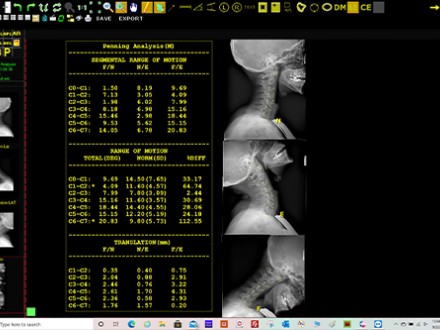

20/20 Imaging Introduces Digital Penning Analysis Tool for Quantifiable Evaluation of Cervical Spine Range of Motion

Once the digital images are acquired and sent to Opal-Chiro, the user selects the tool and annotates the image with the key areas to measure. The software automatically calculates the patient’s range of motion, including flexion to neutral and neutral to extension. Normal values derived from peer reviewed literature are provided for comparison and any deviations are listed, including percent difference. The software also provides alteration of motion segment integrity (AOMSI), an American Medical Association validated method for locating, substantiating and objectively demonstrating the severity of spinal subluxation and any accompanying soft tissue damage.

The new Penning Analysis from 20/20 Imaging for the Opal-Chiro Digital Retrofit DR solution provides quantitative and objective data on flexion/extension motion in 75 to 80 percent less time than a manual workflow.